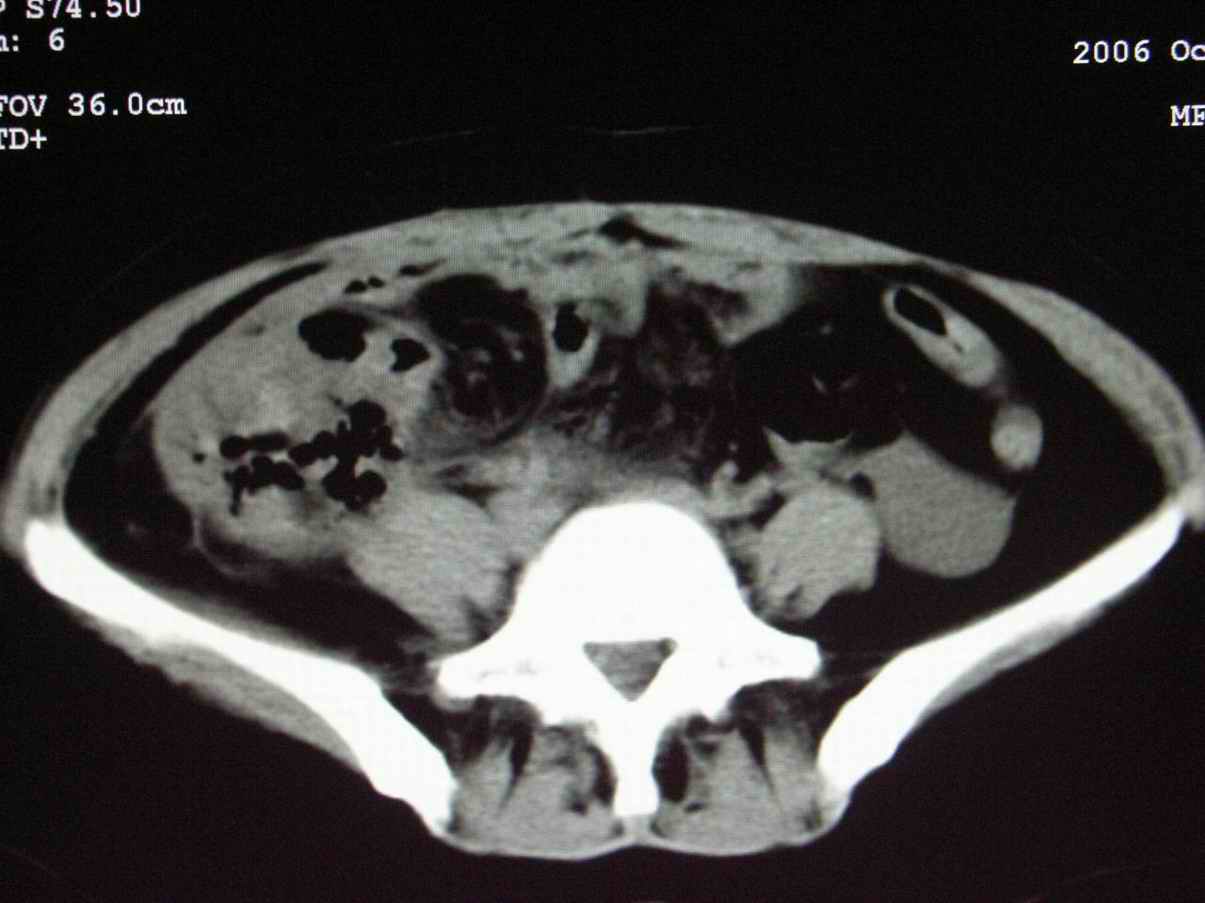

男;67岁,腹胀,腹痛,便血半年;钡餐透视发现右下腹部占位性病变

ct表现;病灶成环状软组织肿块,表现为不对称的肠壁增厚;肠腔变型.

升结肠肠壁不均匀增厚,肠腔变形,支持结肠癌.